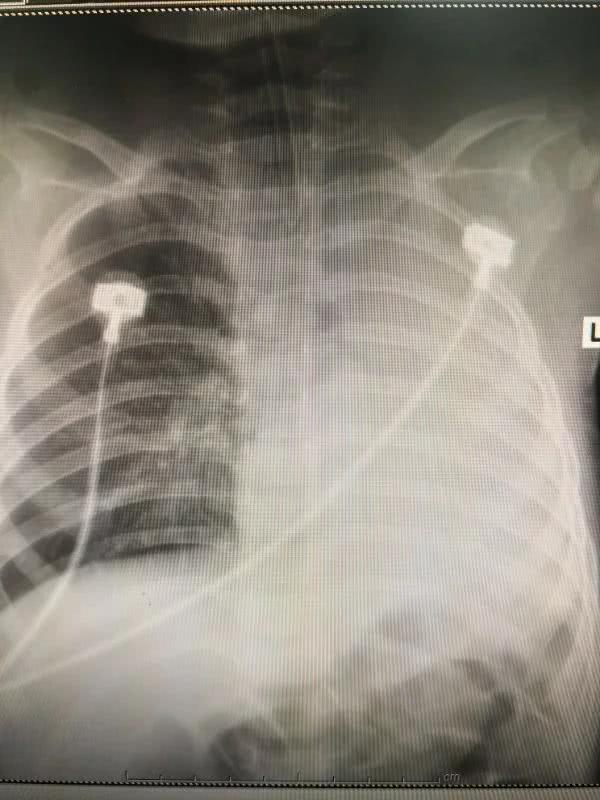

正写着病历的值班大夫叶碧波听见声响,急忙站起身,而此时一行人已经冲进了这间办公室。“当时马上检查了孩子的情况,不太好。”叶碧波称,小雨当时精神差,且出现烦躁、面色发绀、呼吸急促费力、三凹征阳性、心率快、左肺呼吸消失、右肺较多湿啰音等情况,这样的种种表现都反映一个问题,“孩子病情危重,得先转监护室治疗。”

在查了胸部CT后,上述医院的大夫告诉小雨父母,孩子的左主支气管异物堵塞、左肺不张、右肺肺炎,他们医院处理不了,“推荐我们赶快到郑大三附院看。”小雨的家人说道。

“也担心取出时异物脱落移位到健侧肺或者出血,加重病情。”手术困难重重,可也不能不救孩子,在对病情充分评估后,应急治疗小组制定了详尽的治疗方案。手术开始,张艳操作内镜,在小雨的左侧气管内发现异物嵌顿,朱志杰随即操作异物篮,短短1分钟,异物就被取出,并再次进镜抽吸出双侧肺内脓性分泌物,不一会儿,小雨左侧呼吸音恢复,脱离了呼吸机。